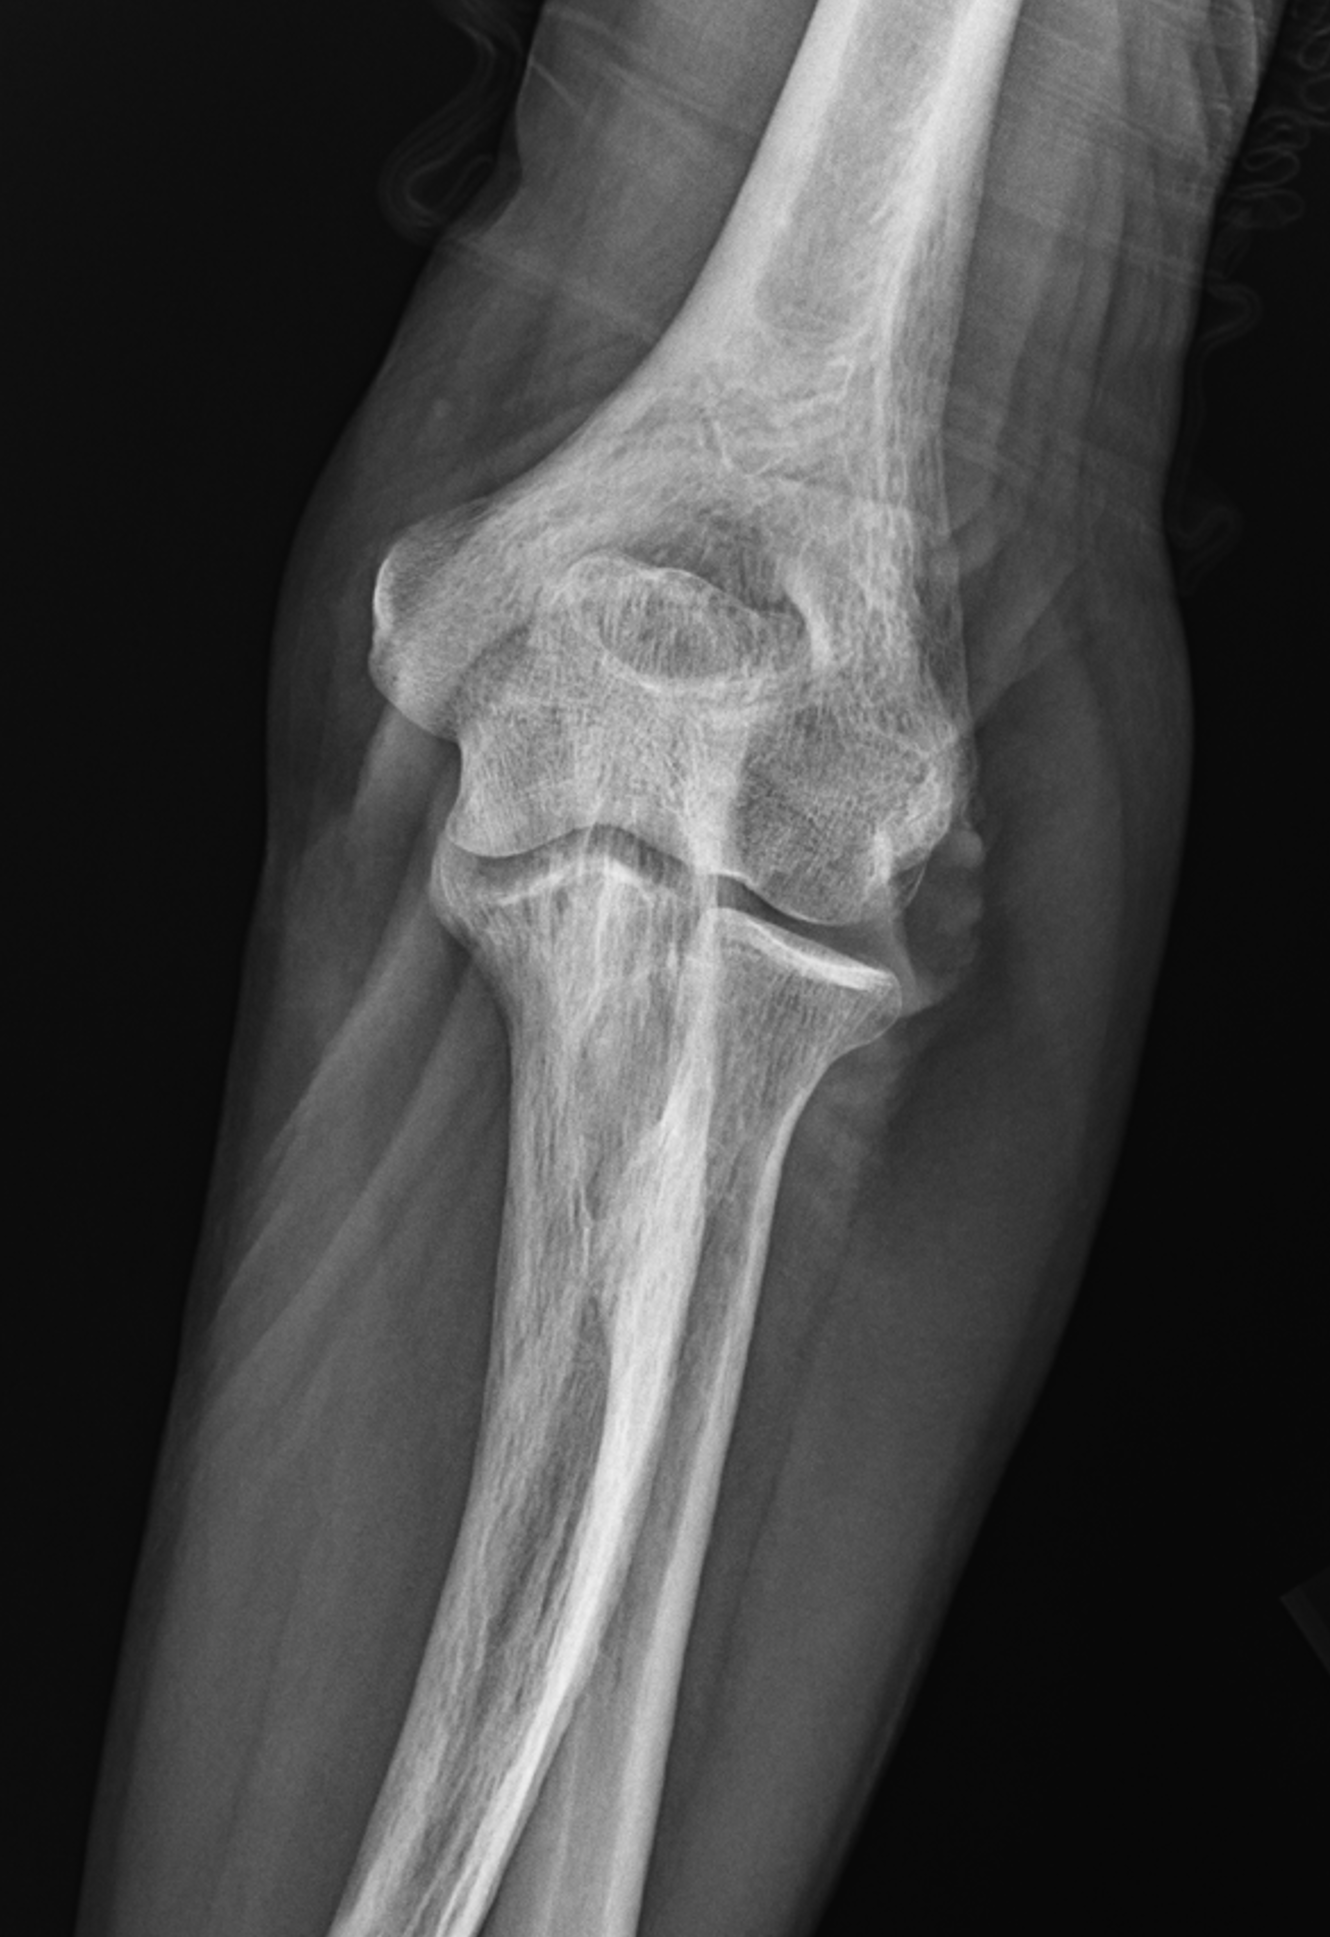

Figure 8: Mixed phase Paget disease in the distal humerus with atypical marrow replacement. (8A) AP and (8B) lateral elbow radiographs show classic findings of Paget disease in the distal humerus, including osseous enlargement, particularly of the medial epicondyle, with associated cortical and trabecular thickening. (8C) T1-weighted and (8D) STIR coronal images show diffusely abnormal marrow signal intensity in the medial humeral epicondyle (asterisks), hypointense compared to skeletal muscle on the T1-weighted sequence and uniformly hyperintense on the STIR sequence. This pattern of marrow replacement is atypical in uncomplicated Paget disease and prompted biopsy, which confirmed the diagnosis. Despite the marrow findings, the radiographic features in addition to the lack of osseous destruction and soft-tissue mass suggest uncomplicated Paget disease and fibrovascular changes. Short interval follow-up to document stability may obviate the need for biopsy in similar cases.

Pattern 3. The least common pattern encountered is during the blastic inactive disease phase with low signal intensity on all pulse sequences suggesting compact bone or fibrous tissue (Figure 9).3,27 Dense sclerosis in the axial skeleton can mimic osteoblastic metastases; accompanying foci of preserved fatty marrow, bone expansion, trabecular coarsening, and stability over time support a diagnosis of Paget disease.